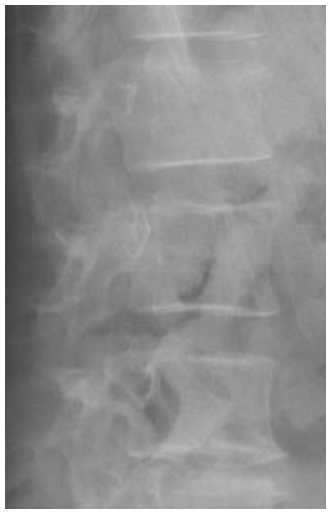

Morphometric fracture was related to radiographic progression. Although it may be surprising that more than 25% of our patients had a morphometric fracture, a previous study found 40% to have vertebral fractures with a higher fracture rate in patients with PsAax than in patients with spondylitis [28]. In patients with spondylitis, the presence of a fracture has been related to greater radiographic damage [29,30]. This fact could be secondary to two reasons: the first one, to the fact that axial immobility associated with radiographic damage would limit the patient's mobility and thereby influence bone fragility. However, it is necessary that other factors intervene in this association because the increase in radiographic progression may not have a significant influence on the mobility of the patient. The second reason, the presence of the syndesmophyte could change different biomechanical parameters that would decrease the resistance of the bone and with it an increase in the presence of fracture. In these cases, the sequence would begin in the syndemophyte and end in the vertebral fracture. We found an inverse relationship: radiographic damage was secondary to the morphometric fracture. Furthermore, individual analysis of the patients showed that some of the vertebrae that were fractured were those that had posterior radiographic progression (Figure 1 and Figure 2). We hypothesize that microtrauma would cause microfractures that would trigger the activation of progenitor cells and their transformation into osteoblasts mediated by bone morphogenetic protein (BMP); thus, the post-fracture remodelling process could participate in the formation of the syndesmophyte [31].